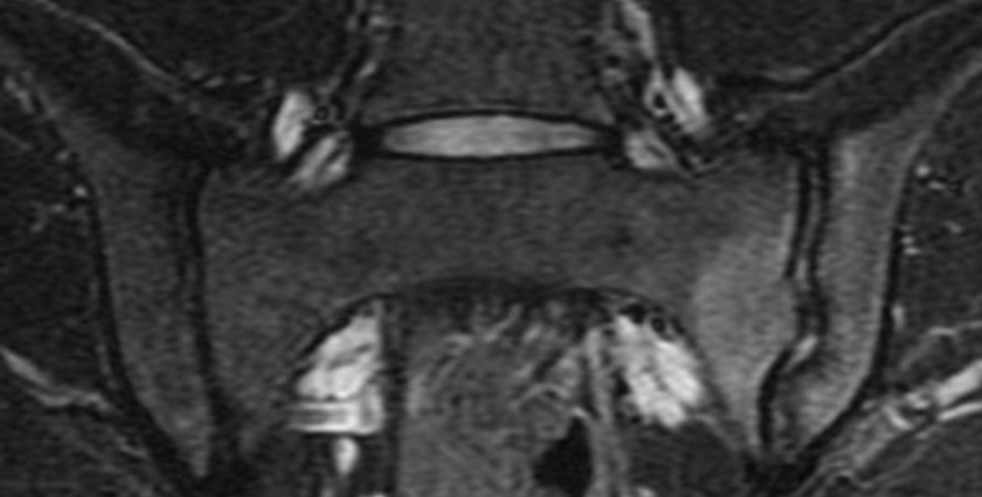

What about sacroiliac joint anatomy? Does it have a normal variation? This study from 2026 looked at the SIJ, and they found 8 different variants, see below (20).

They saw a variant in 3 out of 4 people, the most common was number 4 – a semicircular defect (1 out of 4 had this), and number 2 – iliosacral complex complex (1 out of 5). Again, a proof that we’re all build different, and this is normal!